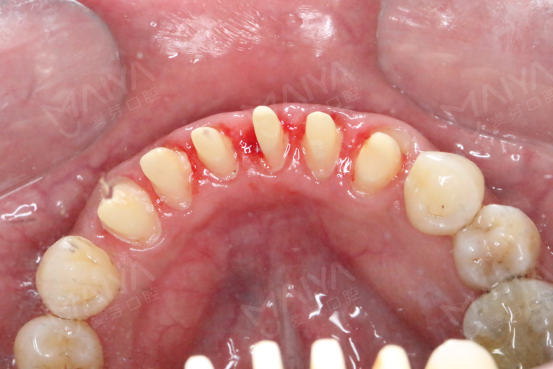

1、将牙龈作激光环切处理,同时上下颚的烤瓷牙做拆冠制作,按照色标的参数值,初步检查咬合接触关系。

修复后的牙齿

初步检查咬合关系 逐一测量基亚冠修复空间